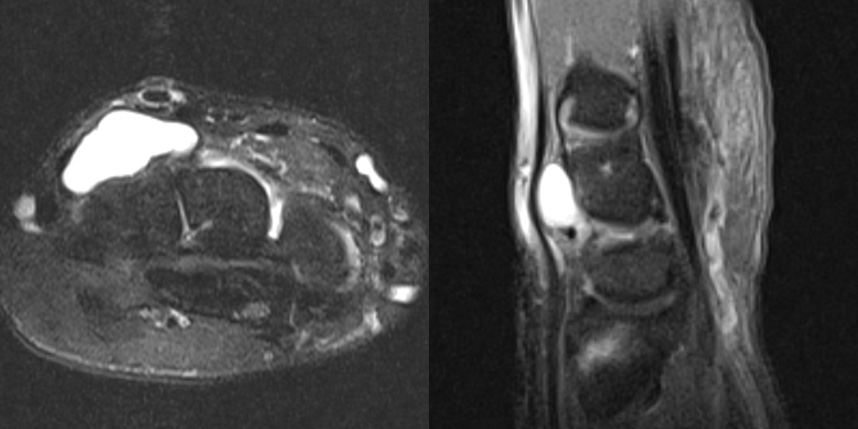

손목 앞쪽의 결절종이 있었지만, 뿌리는 손등쪽하고 연결된 까다로운 경우의 MRI 입니다.

만약 MRI 를 찍지 않았다면 손목 앞쪽에 보이는 결절종만 제거하여 재발 가능성이 높을 수 있는 경우입니다.

이 환자의 경우 앞, 뒤에 절개를 넣어 뿌리까지 제거해주어 재발 없이 유지되었습니다.